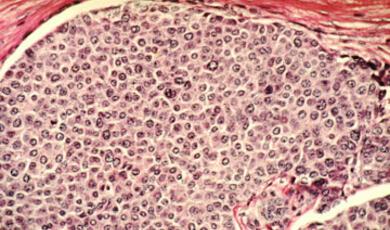

Different cancers offer differing hopes of prevention; from cervical or lung cancer (which are completely or largely preventable), to prostate cancer (for which there is no current strategy). What can be done, and what does the future hold?